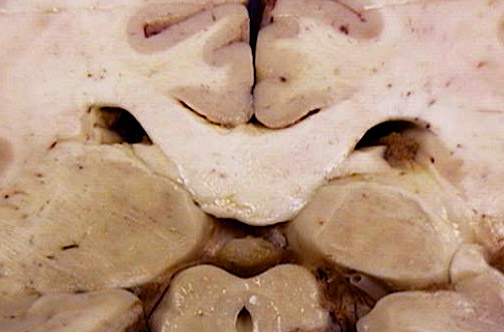

Identify the following regions of the normal brain by clicking in the image below:

Aqueduct of Sylvius - Pulvinar of Thalamus - Cingulate Gyrus - Choroid Plexus - Pineal Gland - Splenium of Corpus Callosum - Collicular Plate